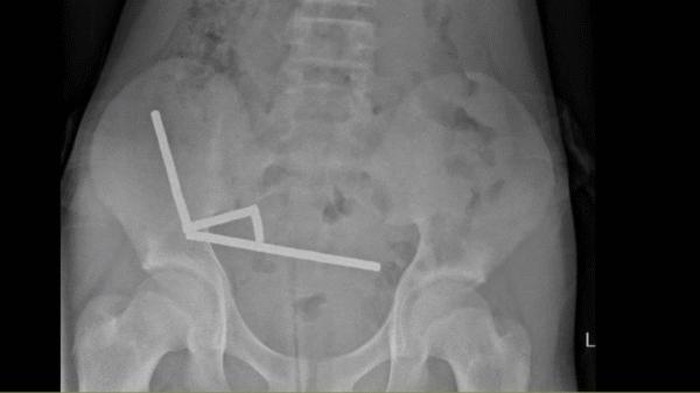

Ditulis Science Alert, magnet-magnet itu kemudian bersatu dan menghancur dalam tubuh bocah tersebut. Dengan menggunakan sinar X, dokter melihat empat rantai linier di bagian terpisah pada usus anak laki-laki itu.

Selama operasi, rantai-rantai tersebut ditemukan di beberapa bagian usus halus dan sekum. Rantai-rantai tersebut saling menekan dan menyebabkan beberapa bagian jaringan mati karena kekurangan darah, yang dikenal sebagai nekrosis tekanan.

Remaja 13 tahun asal Selandia Baru menelan hampir 200 magnet yang sangat kuat. Akibatnya, dia harus kehilangan sebagian ususnya. Foto: Lekamalage et al., NZMJ, 2025 |